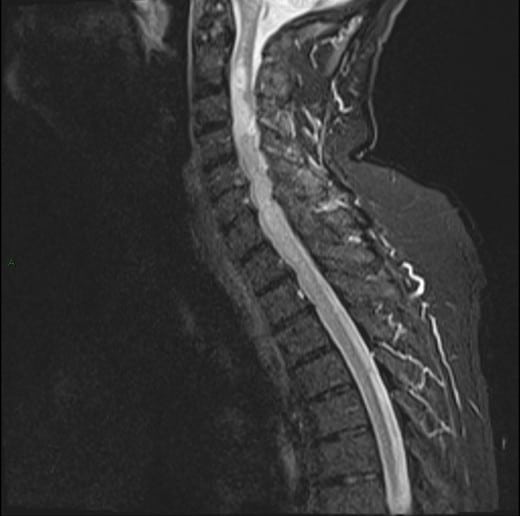

U tủy sống

» Thông tin: Nam giới – 70 tuổi.

» Lâm sàng: Yếu vai phải.

# U sao bào tủy sống (Spinal Astroctyoma) ngang mức C2-C4.